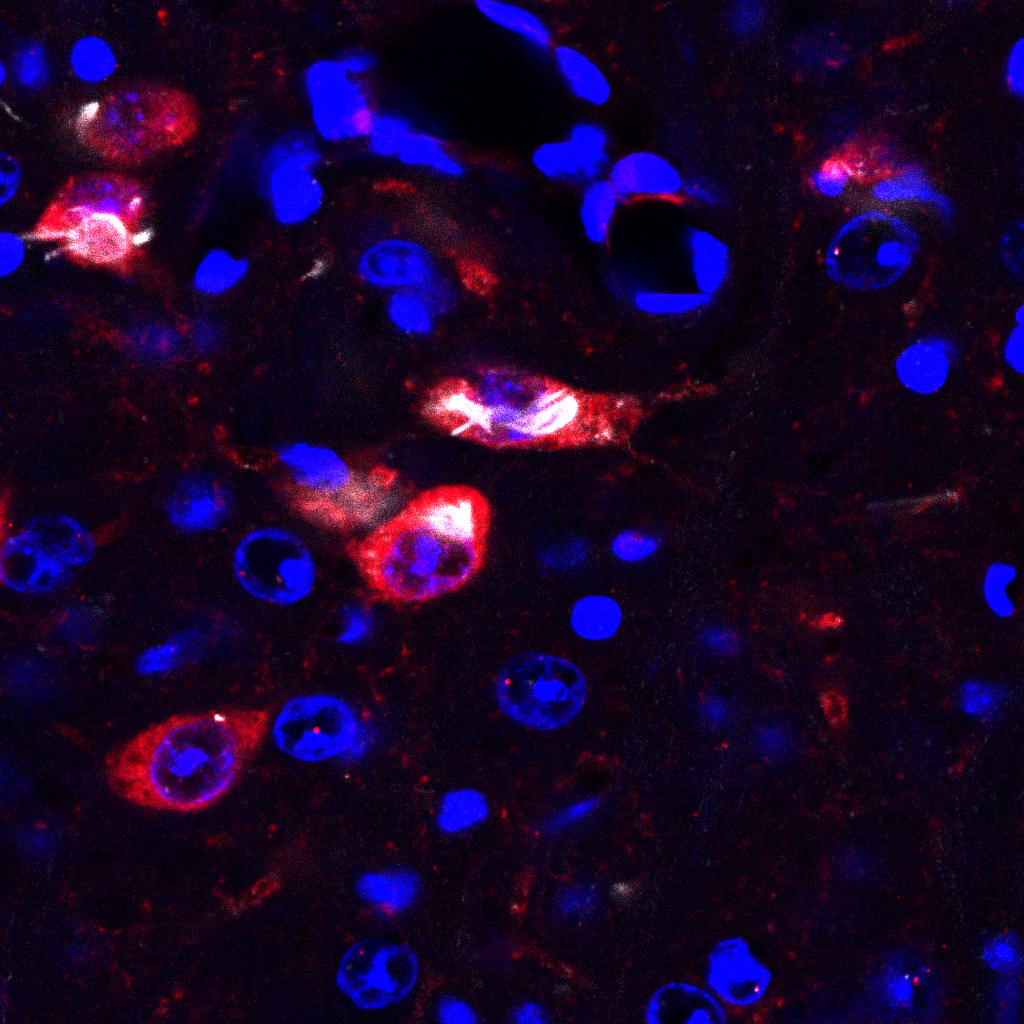

Intracellular aggregation of the small protein α-synuclein is a hallmark of Parkinson’s disease and thought to be responsible for the progressive loss of neurons. By combining up-to-date biosensors with two-photon-laser-scanning-microscopy we investigate how Lewy pathology causes neurons to die in Parkinson’s disease.

By combining redox-sensitive biosensors with two-photon-laser-scanning-microscopy the oxidative state of neurons can be measured.